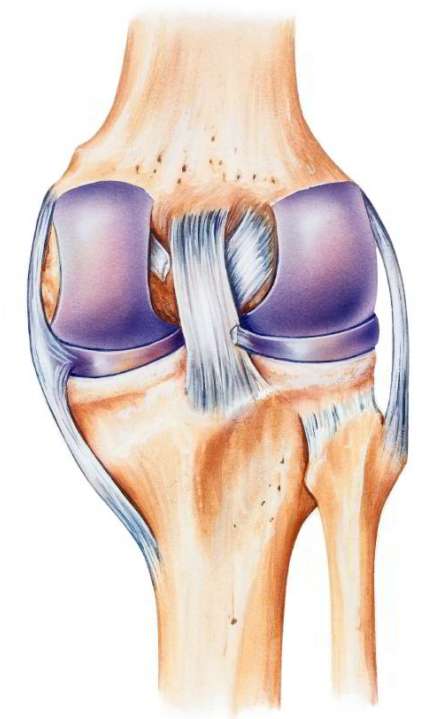

Zentral im Kniegelenk kreuzen zwei Bänder, die Oberschenkel (Femur) und Schienbein (Tibia) miteinander verbinden und in ihrer Position halten – das vordere Kreuzband und das hintere Kreuzband. Durch einen Kreuzbandriss (Ruptur des Kreuzbandes) wird das Kniegelenk instabil. Ursächlich sind meist ein traumatisches Umknicken oder eine Verdrehung (Distorsion) des Kniegelenks. Dadurch entsteht eine Instabilität zwischen Oberschenkel- und Unterschenkelknochen. Der Oberschenkelknochen (Femur) schiebt sich dann nach vorne über das Schienbein (Tibia) hinaus.

Funktion der Kreuzbänder im Knie

Um die Spätfolgen des Kreuzbandrisses besser zu verstehen, muss man sich die Funktion der Bänder im Knie anschauen. Im Kniegelenk sind Oberschenkel (Femur) und Unterschenkel (Tibia) über vier Bänder miteinander verbunden: Zentral im Knie verlaufen das vordere und hintere Kreuzband und die beiden Seitenbänder stabilisieren das Gelenk innen und außen.

Die Kreuzbänder halten das Kniegelenk bei jeder Belastung in seiner Position. Sie verlaufen im Inneren des Gelenks und überkreuzen sich dabei. Die beiden Bänder sind also die zentralen Stabilisatoren des Kniegelenks.

Das vordere Kreuzband besteht aus zwei relativ unabhängigen Faserbündeln. Diese Bündel sind spiralförmig verdrillt. Das macht das Kreuzband belastbar gegenüber den verschiedenen Kräften, die im Alltag auf das Kniegelenk einwirken.

Das hintere Kreuzband verhindert, dass das Schienbein nach hinten unter den Oberschenkelknochen gleitet. Das vordere Kreuzband verhindert, dass der Oberschenkelknochen über das Schienbein hinweg nach vorne ausweicht.

Die Kreuzbänder zentrieren die Knochen im Kniegelenk

Sowohl das vordere als auch das hintere Kreuzband stehen ständig unter einer gewissen Spannung. Sobald man das Kniegelenk belastet, sorgen sie für eine Zentrierung der Knochen im Kniegelenk. Sie schränken also die Beweglichkeit der oberen und unteren Gelenkfläche gegeneinander stark ein. So zentrieren die Bänder das Kniegelenk bereits, bevor die Muskeln bei einer Belastung als Stabilisatoren einspringen können. Die Muskeln im Bein rund um das Kniegelenk reichen ohne die Funktion der Kreuzbänder nicht aus, um eine Überbeweglichkeit des Kniegelenks zu verhindern.